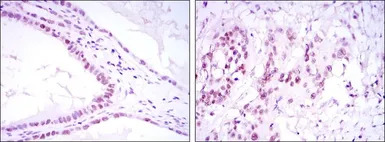

IHC-P analysis of kidney convoluted tubule tissue (left) and esophageal cancer tissue (right) using GTX60380 SUZ12 antibody [3D10].